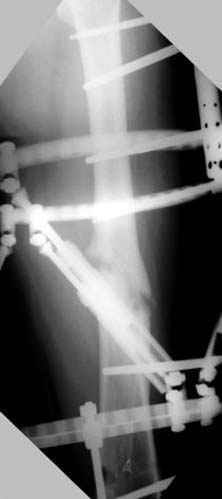

Несколько снимков из моей коллекции, чтобы разьяснить, почему мы до сих пор делаем различные варианты остеотомии.

N3 рисунок окончательный снимок, после операции моя рентгенограмма должен выглядеть примерно как эта картина. На N4 снимке клин перед удалением; N5 послеоперации 3 нед.; N6 окончательная рентгенограмма.

Отправитель: Djoldas Kuldjanov 23 Ноябрь 2004, 18:21

пластическая модель; и коррекция бедра аппаратом Илизарова.

Имею другие снимки тоже, получится как отчет о моей работе.